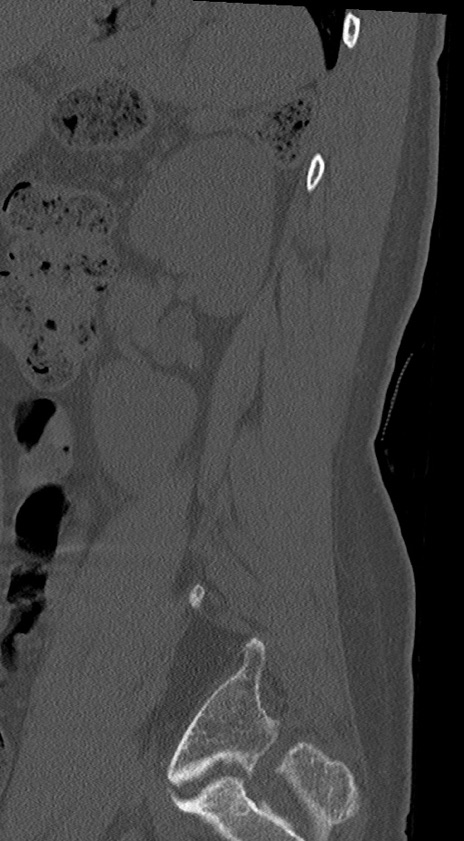

腰椎CT

冠状断像